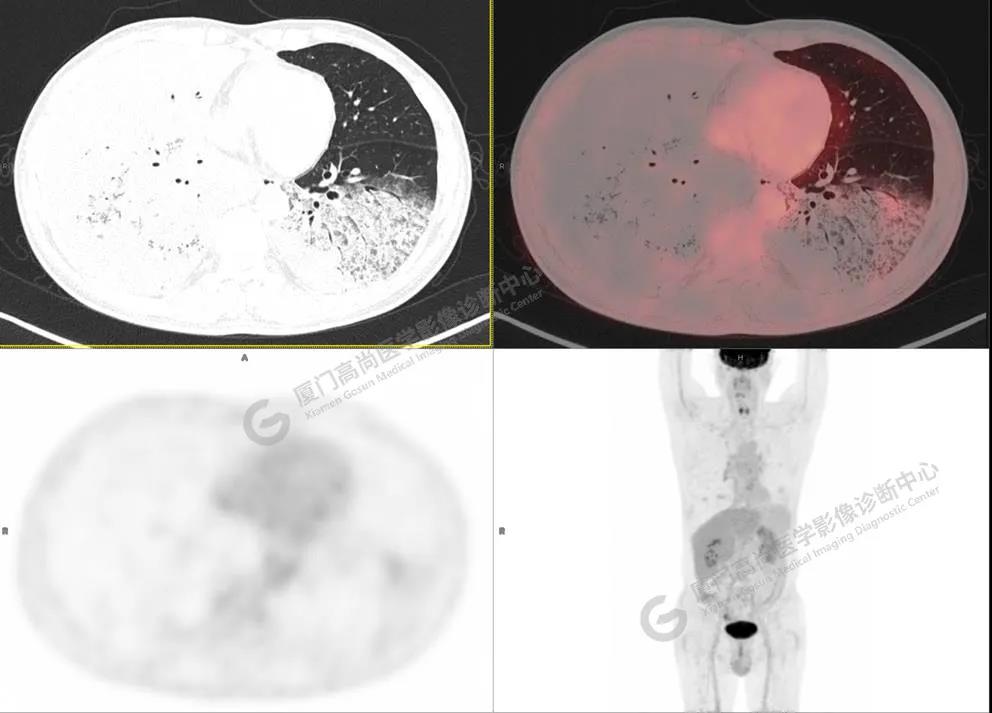

PET/CT影像圖

圖3

PET/CT所見(jiàn):雙肺大片實(shí)變影及磨玻璃影,部分呈地圖樣改變,累及右肺尖,部分放射性攝取輕微增高,SUVmax 1.77,其內(nèi)見(jiàn)多發(fā)支氣管充氣征象。

影像診斷: 雙肺大片實(shí)變影及磨玻璃影,大部分代謝不高,局部代謝輕微增高,考慮肺泡蛋白沉積癥,建議病理學(xué)檢查或肺泡灌洗物檢查。